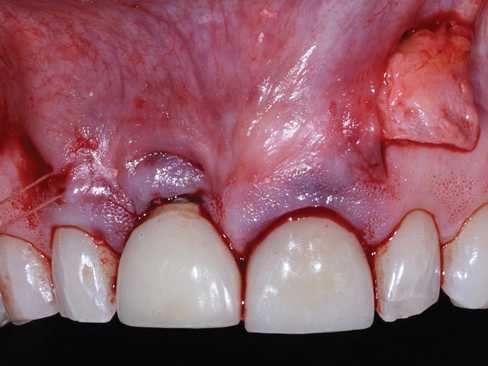

Envelope flaps,15 which are one of the most common flap designs, have the advantage of simplicity, blood supply, sulcular access to the roots to address NCCLs or for root preparation, and predictable root coverage (Figure 1). Because this flap design involves reflection of the papillae, it may affect papillary height upon healing. Envelope flaps may be utilized with vertical releasing incisions as a variation.

(1.) Example of an envelope flap, which offers the advantages of simplicity, blood supply, sulcular access to the roots to address NCCLs or for root preparation, and predictable root coverage.

Figure 1